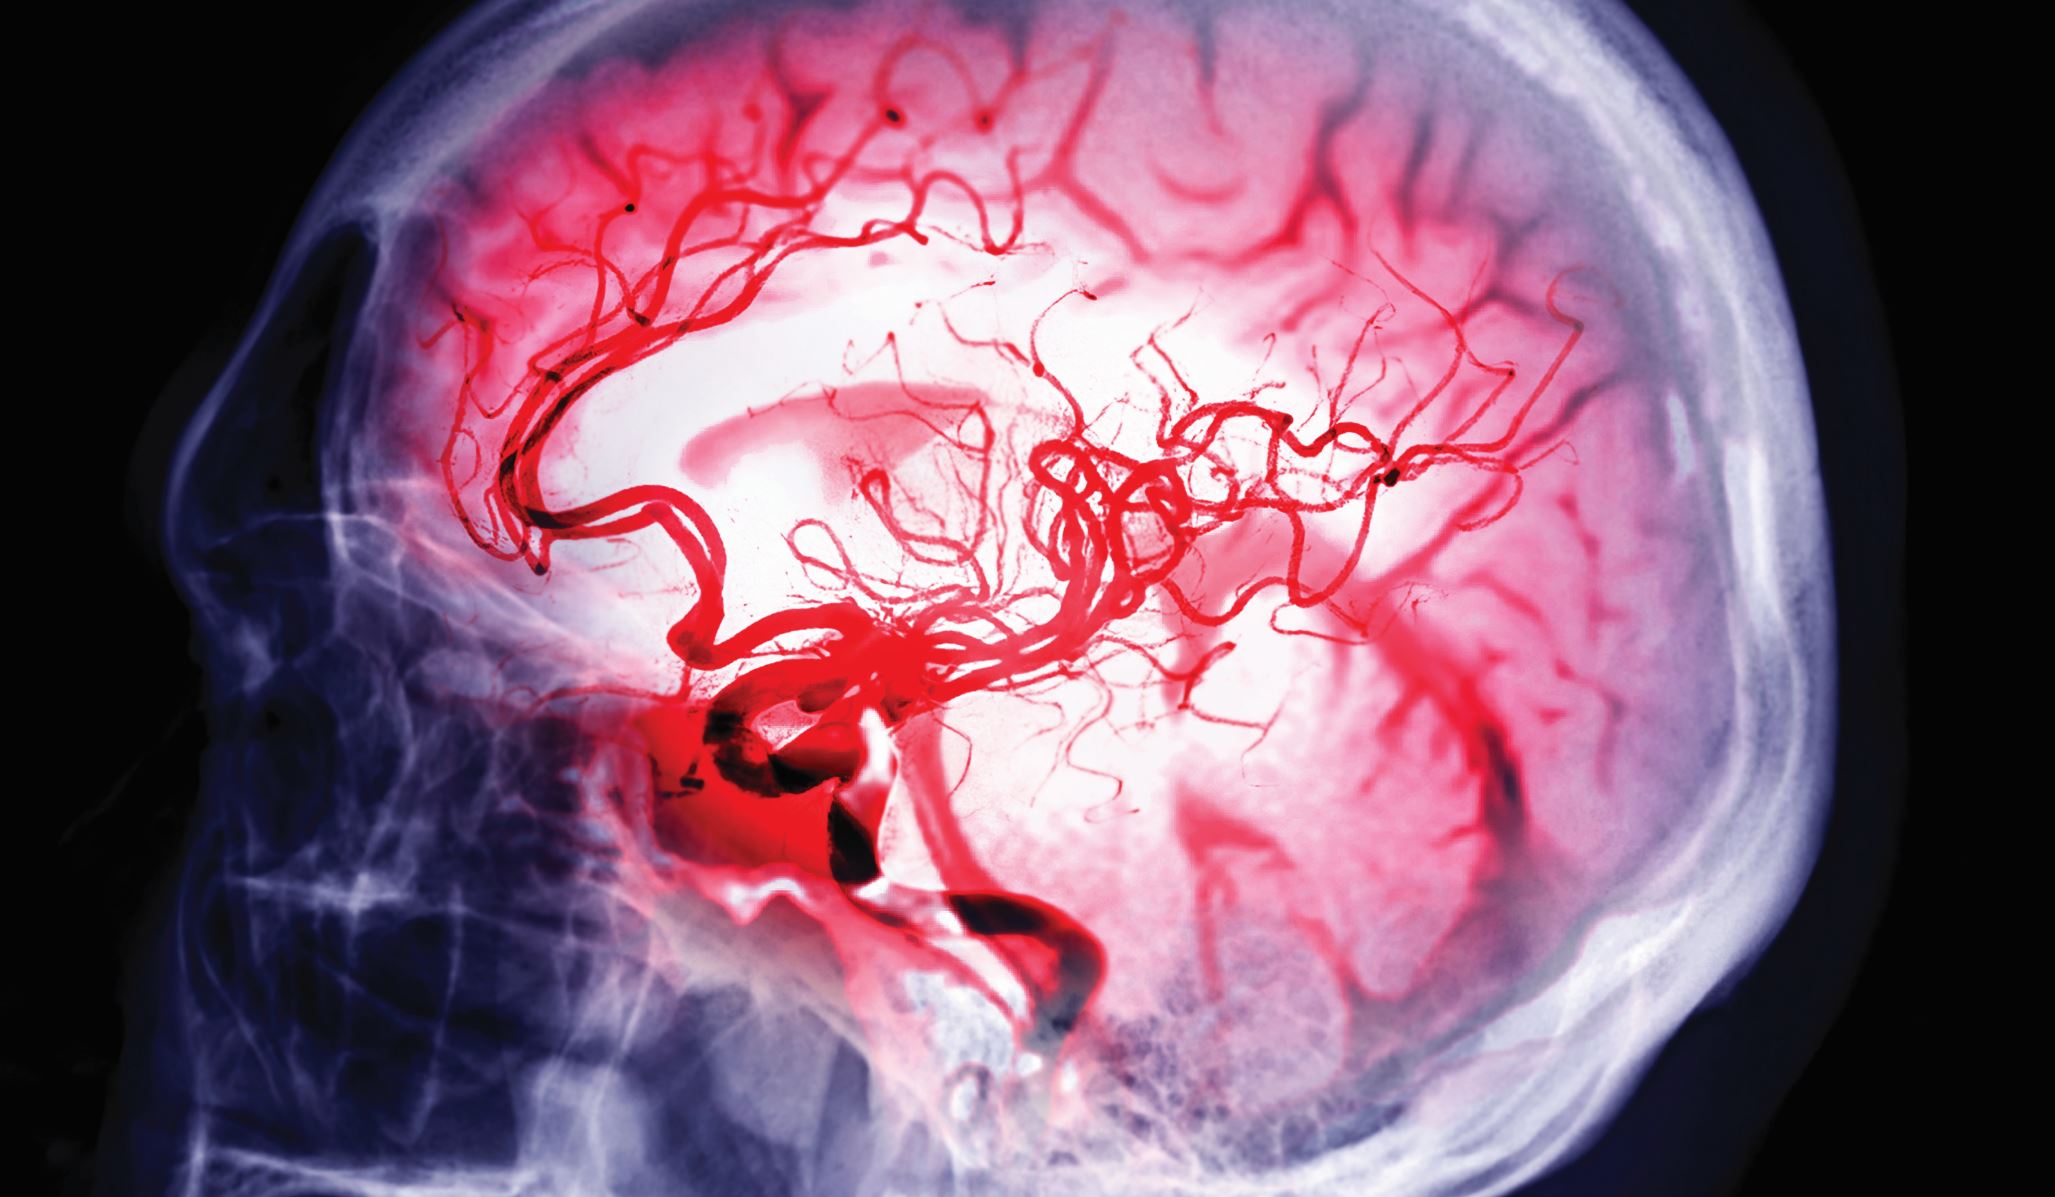

Die Entscheidung, wann und wie nach einem ischämischen Schlaganfall bei Patientinnen und Patienten mit Vorhofflimmern wieder antikoaguliert werden soll, ist nicht trivial. Eine evidenzbasierte Entscheidung muss das Blutungs- und Embolierisiko berücksichtigen. Patientenindividuelle Risikofaktoren spielen hierbei eine bedeutende Rolle. Diese Übersicht fasst die aktuelle Studienlage sowie abgeleitete Empfehlungen für die Praxis zusammen.

Tritt bei Vorhofflimmern ein ischämischer Schlaganfall auf, muss die Strategie der Antikoagulationstherapie überdacht werden.